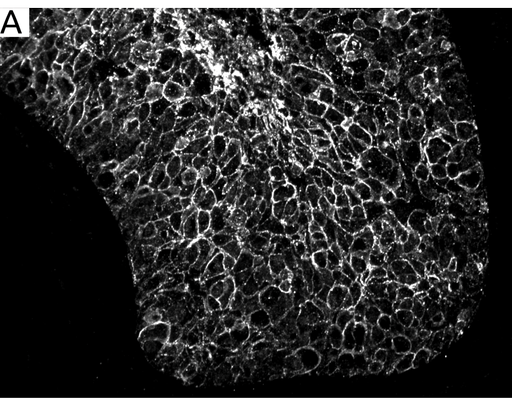

Figur 1. Jämförelse mellan Lumitos UCNP-infärgning och standard immunohistokemisk DAB-infärgning.

I bild A är bröstvävnad infärgad med Her2-UCNP–reagens för att visualisera celler med förekomst av Her2, en vanlig markör vid diagnos av bröstcancer.

Bild B visar infärgning i samma vävnadsprov som i bild A, men med standard DAB-infärgning. Både bild A och bild B visar jämförbar detaljeringsnivå men både bakgrundssignal och autofluorescens är eliminerade i Lumitos UCNP-baserade infärgning. Eliminering av all oväsentlig information från bakgrundssignal och autofluorescens ger väsentligt bättre förutsättningar för automatiserad analys baserat på t ex AI-algoritmer.